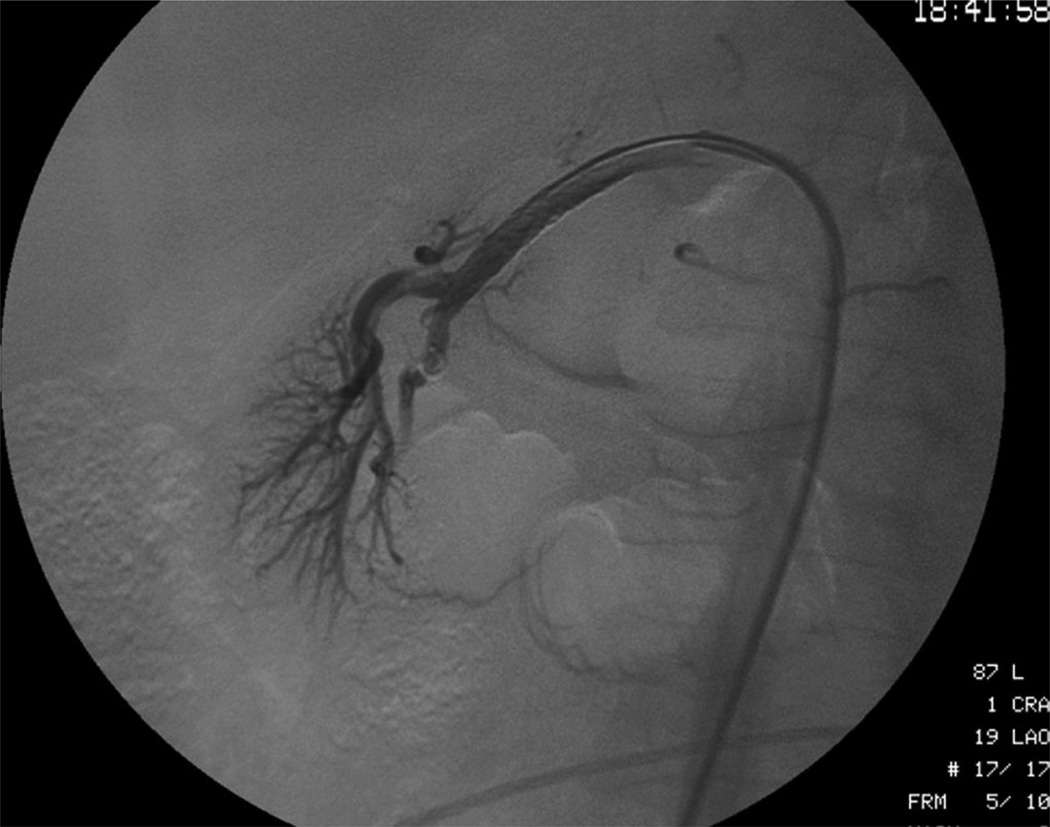

Fig. 2.

Angiography of the renal arteries verifying occlusion of flow through the right renal artery (arrow).

A 43-year-old female motorcyclist sustained blunt trauma and presented with abdominal, chest, and extremity pain. Physical examination was significant for an acutely tender abdomen. Serum chemistries and hematocrit were within normal limits. Gross blood was not present on Foley catheter insertion, but urinalysis revealed microscopic hematuria. A computed tomography scan showed the right kidney was nonperfused; indicating a grade V injury (Fig. 1). No perinephric hemorrhage or retroperitoneal fluid was noted. In addition, a grade IV liver injury and a grade I splenic laceration were present. After consultation between the urology, trauma, and interventional radiology service, a laparotomy was deemed inadvisable because of the likelihood of massive liver bleeding. A diagnostic angiography, however, showed no active extravasation from the liver and an abrupt cut off of the injured right renal artery (Fig. 2). A hydrophilic guidewire was used to cross the thrombosed vessel. Two overlapping Cordis Genesis PG244B stents (Johnson and Johnson, Warren, N.J.) were deployed on a high-pressure angioplasty balloon. Repeat angiography revealed restored blood flow to the kidney with no residual intraluminal defect (Figs. 3 and 4). The hepatic and splenic injuries were managed nonoperatively. Given this concomitant trauma, no anticoagulation or antiplatelet therapy was initiated after stent placement. On postoperative day three, the patient’s serum creatinine doubled. Renal ultrasound demonstrated an absence of flow to the right renal artery. The patient’s creatinine peaked at 2.8 and later normalized to 1.2. A 1-month follow-up computed tomography scan and lasix MAG-3 renal scan, respectively, showed patchy contrast uptake and 5% relative function in the stented kidney.